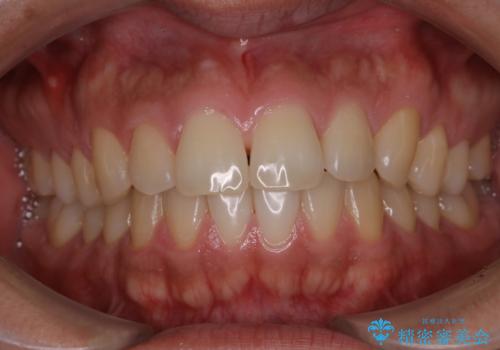

電子タバコによる着色をPMTCできれいに落とす

- 1日に10本くらい電子タバコを吸うため、歯の黄ばみ・着色が気になるとのことでした。PMTC30分コースを行いました。

タバコに含まれているものの中で、タールというものが歯の黄ばみの原因です。その黄ばみなどを、無理に落とそうとしたりすると歯の表面に傷がついてしまったり余計に汚れがつきやすい状態になることがあります。

PMTCでは、歯の表面の凸凹にミネラルを補給して、ツルツルの表面に仕上げます。定期的にPMTCを行うことにより、歯質の強化になり着色がつきにくい状態になります。

普段の飲食物・歯磨き・生活習慣・喫煙の有無などにより着色の付き具合には個人差があります。どれくらいの頻度で行うことがベストかは、その都度担当の歯科衛生士とご相談します。